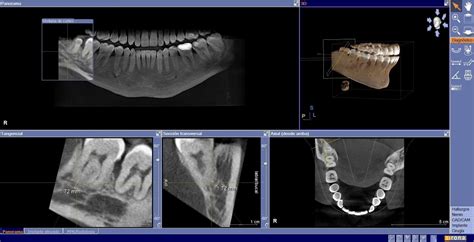

Un TAC dental consiste en una exploración con rayos X para obtener imágenes de las estructuras dentales, tejidos blandos, nervios y huesos de la cabeza. Con los datos obtenidos, el doctor podrá utilizar las potentes herramientas digitales que ofrece el software para realizar un diagnóstico más exacto.

- Mejora y aumento de la precisión: Gracias a esta tecnología obtenemos un escáner perfecto de la dentición de nuestros pacientes; consiguiendo imágenes en tres dimensiones de sus dientes y huesos maxilares.

La principal diferencia entre un TAC dental y una radiografía dental es que el TAC produce una amplia variedad de vistas y ángulos tanto en 2D como en 3D en alta resolución que permite observar con detalle las zonas exploradas.

La mayor diferencia entre ellas es que las imágenes que se consiguen con la radiografía panorámica son en 2D mientras que el TAC dental es una técnica radiológica en 3D.